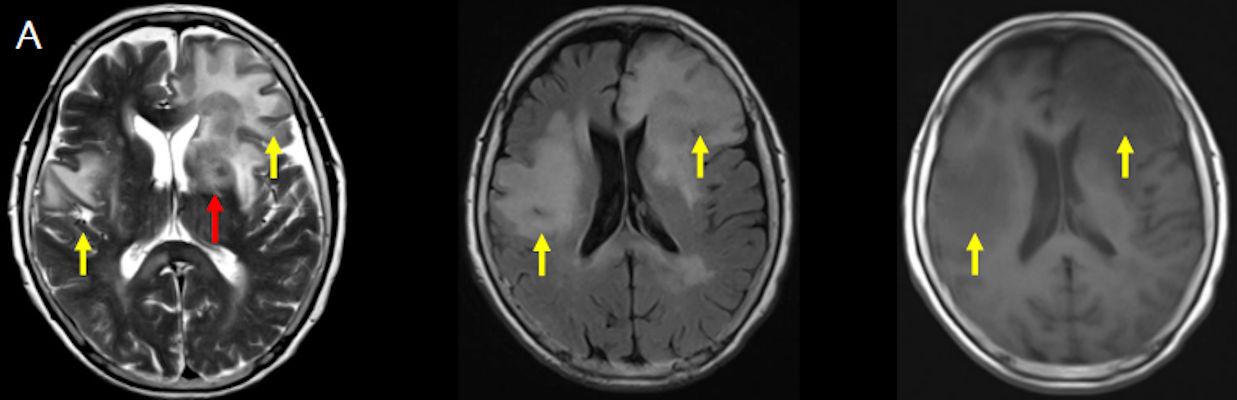

- (A) Her iki periventriküler beyaz cevherde aksiyel T2A, FLAIR serilerde hiperintens, T1A hipointens geniş ödem alanları (oklar) izlenmektedir. Sol frontalde T2A’da hipointens kitle lezyonuna (ok) dikkat ediniz.

- (B) Aksiyel postkontrast T1A görüntülerde büyüğü sol frontalde kontrastlanma gösteren multipl kitle lezyonları (oklar) izlenmektedir.

- (C) Difüzyon ağırlıklı görüntülerde sol frontaldeki kitle lezyonunda difüzyon kısıtlama bulgusu (oklar) mevcut olup perfüzyon MRG’de rCBV haritasında belirgin perfüzyon artışı izlenmemektedir (ok).